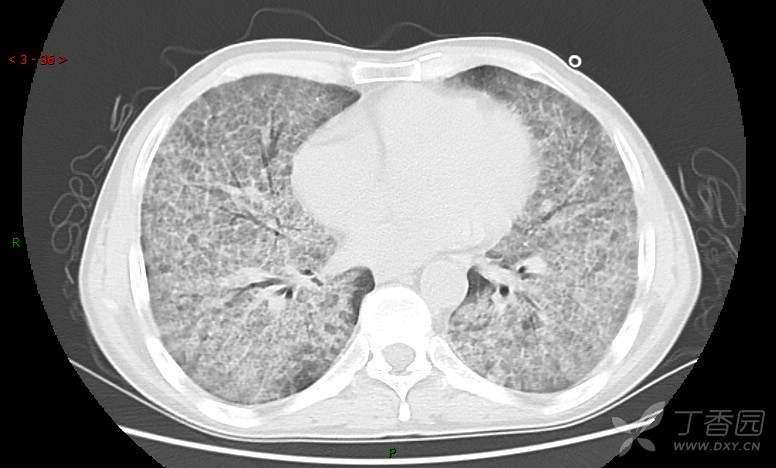

地图+铺路石征=PAP?那升高的CEA怎么说(病例3连发,附其他2例链接)

患者男,42岁,咳嗽半年余,加重伴憋喘2月余。

患者半年余前无明显诱因出现间断咳嗽,干咳为主,偶咳少量黄白痰,剧烈咳嗽或运动后可出现轻度憋喘,无高热、脓臭痰,无胸痛、咯血及晕厥,无低热乏力及盗汗,无心前区压榨感及夜间阵发性呼吸困难,初未在意,未予正规诊治。2月余前患者自觉上述症状较前加重,咳嗽、憋喘明显,黄白色粘痰略有增多,伴有发热,热前伴有畏寒、寒战,体温最高达38.9℃,先后就诊多家医院,入住重症监护室,未行气管插管,考虑“重症肺炎”,给予“美罗培南、复方磺胺甲噁唑”等药物抗感染,“卡泊芬净”抗真菌,并给予“甲泼尼龙”等药物治疗35天,经治疗后症状好转于2018-04-02出院。患者自出院后仅应用中药治疗(具体不详),并给予家庭氧疗,平素仍有间断咳嗽,咳少量黄白色粘痰,活动后憋喘明显,活动耐量差,以卧床为主。